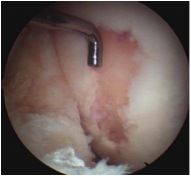

Arthroscopic microfracture awl / 1.6 mm drill

- typically 3-4 mm apart

- depth until see fat globules

Debride all unstable cartilage to stable edge

- removed calcified cartilage layer with curette, protect subchondral bone

- create a perpendicular edge which helps to hold the clot